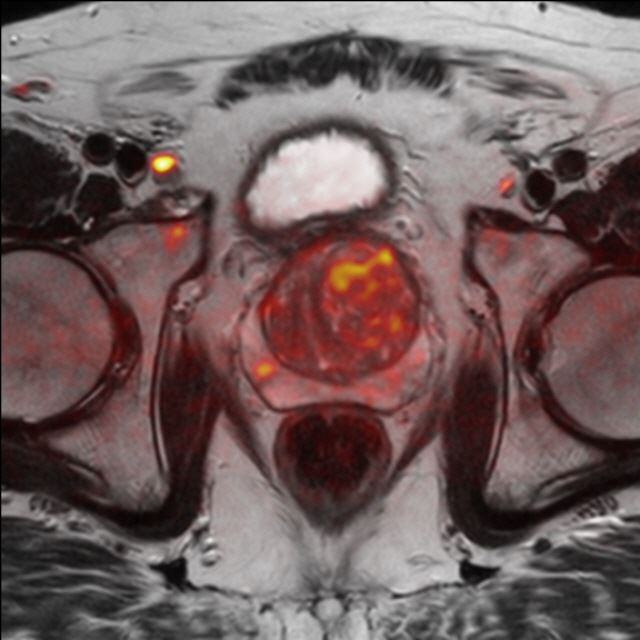

Prostata (mpMRT)

Die multiparametrische MRT der Prostata (mpMRT) bietet eine gute Möglichkeit, mittels bildgebender Diagnostik die Lokalisation, die Ausdehnung und eventuelle Aussaat eines Prostata-Karzinoms darzustellen.

Bei fehlender Darstellung des Tumors im Ultraschall oder vergeblichen Biopsien kann die MRT als Problemlöser eingesetzt werden: Sie zeigt dem Urologen, wo eine weitere Biopsie die Diagnose sichern kann. Außerdem kann die MRT bei sehr ausgedehnten Tumoren einen Überblick über die Beteiligung der Nachbarorgane verschaffen und Absiedlungen (Metastasen) entdecken.